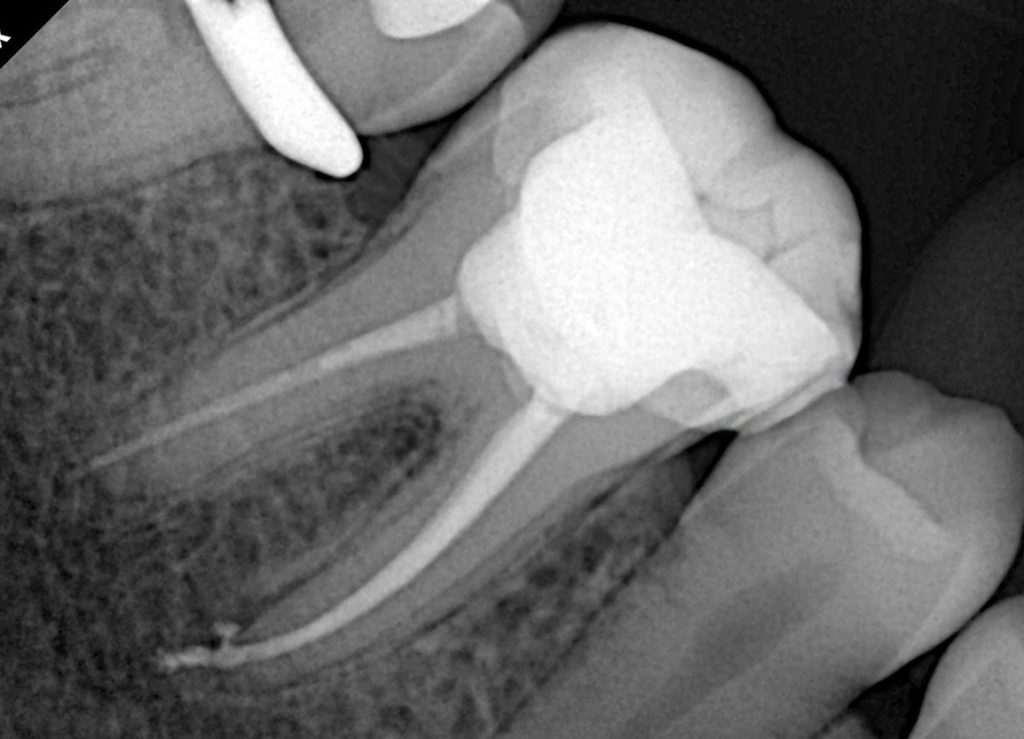

- Clear 3D fill visible in postoperative radiographs.

4. Coronal Seal – Start of Biomimetic Dentistry

Why immediate seal?

To block coronal micro-leakage and reinforce internal cusps.

- Pulp chamber sandblasted + etched + universal adhesive (scrubbed 20 sec).

- Floor sealed with a thin layer of flowable composite.

- Deep dentin replaced using GC EverX Posterior fiber-reinforced composite—mimics dentin modulus and prevents crack propagation.

- Occlusal enamel anatomy layered with a nano-hybrid composite for shade and gloss.

- Clean radiographs with excellent obturation length and density

- Proper coronal seal with fiber reinforcement